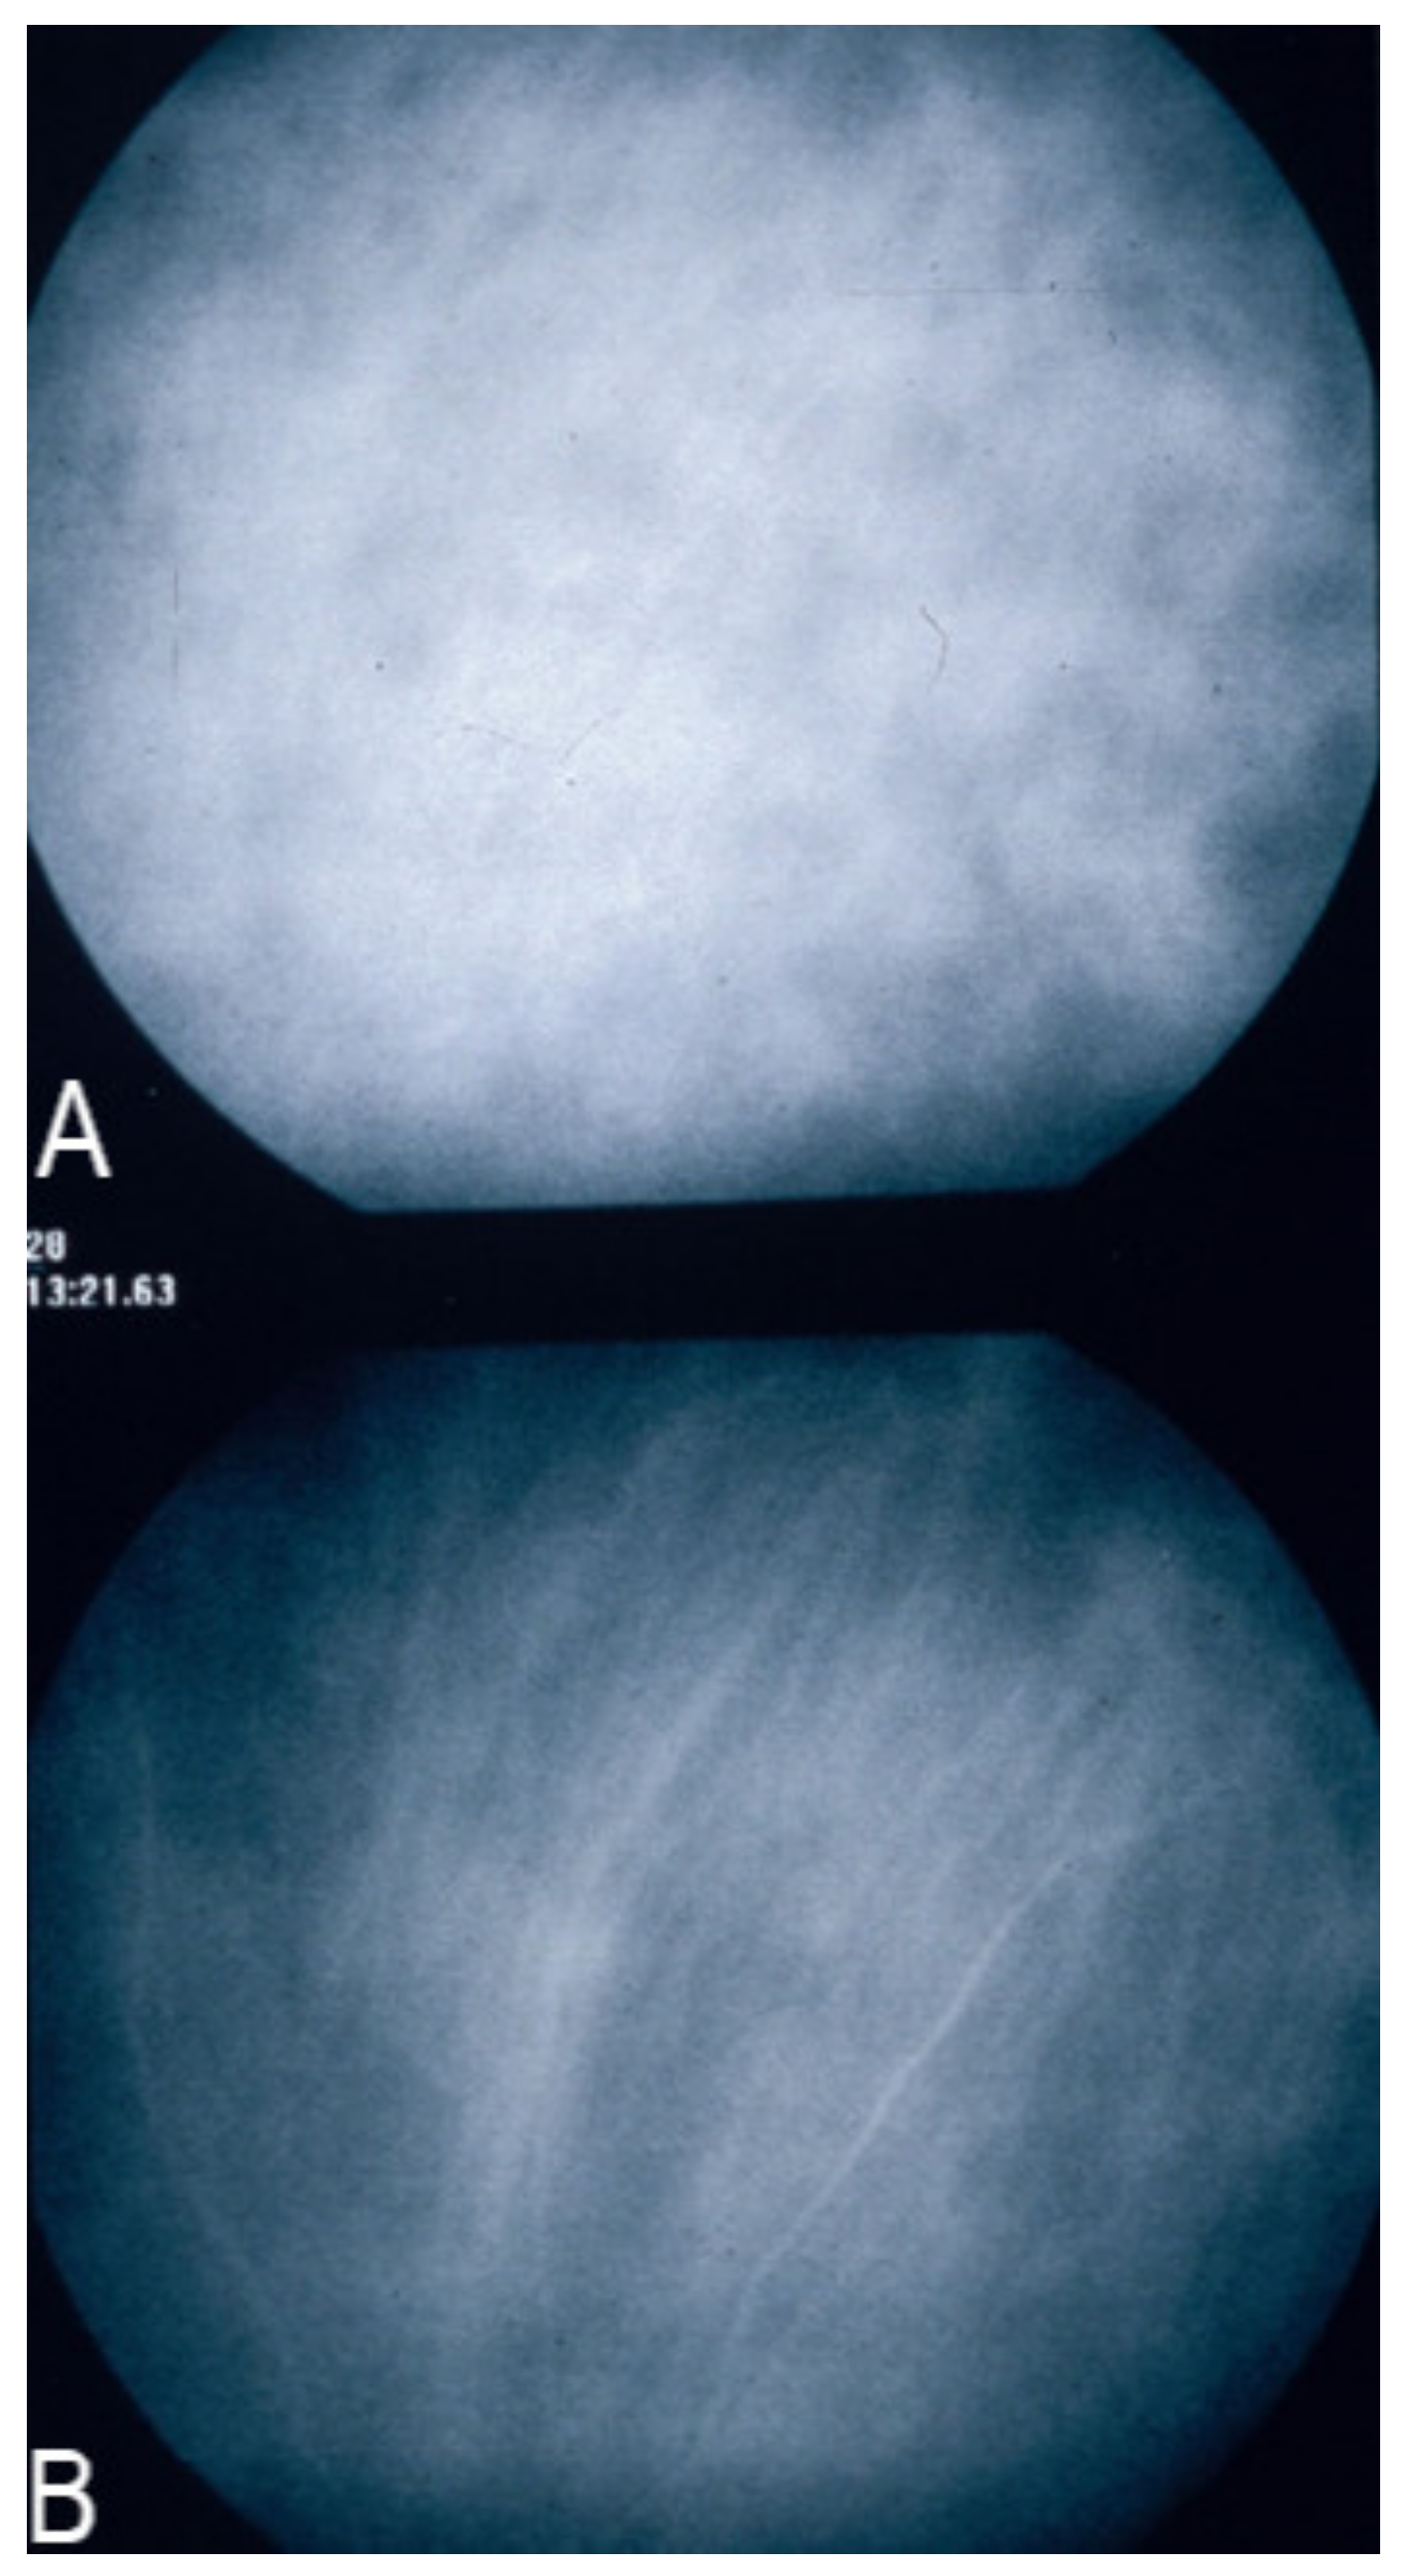

After intravenous injection of the ICG dye, fluorescence is obtained by shining a light beam inside the eye towards the fundus. Maximum absorption of the molecule occurs at around 800 nm, followed by fluorescence emission at around 830 nm. These infrared frequencies penetrate and reach the choroid through the RPE and conversely fluorescence produced by the ICG molecule can be detected through the RPE by appropriate angiography cameras. Fluorescein sodium produces fluorescence when excited by light frequencies in the visible light spectrum, which are stopped by the RPE. Therefore, FA cannot give information on the choroidal structures, while ICGA is detecting fluorescence coming from the choroid. (Figure 1) Some authors started to call this phenomenon cyanescence, which is a useless terminology, as the basic optical mechanism is fluorescence in both situations.

2.1.2. Macromolecular Behaviour of the ICG Molecule

The second crucial characteristic of the ICG molecule is that it is bound up to 98% to large plasma proteins (80% to globulins and 20% to alpha-lipoproteins and albumins). ICG has a molecular weight of 775 Daltons (d), not much more than the fluorescein molecule (332 d). The difference, however, lies in the fact that, being tightly bound to large proteins, it forms a large molecular complex with a molecular weight of over 60 to 80,000 d. This means that ICG will remain within the vessels of the retina, which have tight junctions. In the choroid also, ICG will remain within large vessels. However, this large molecular complex will escape from the fenestrated choriocapillaris and will shed into the choroidal space and remain trapped as wash-out will be slow because of the size of the molecular complex. (Figure 2) Consequently, analysis of ICGA fluorescence is more focussed on the choriocapillaris flow and the subsequent impregnation of the choroidal space by the ICG molecular complex than the intravascular fluorescence. It is by analysing the pattern of Impregnation of the choroidal space and its disturbance that ICGA made it possible to classify choroiditis and its different mechanisms.